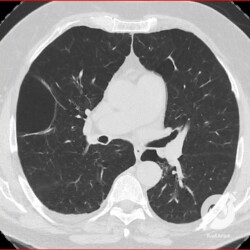

Esta é uma tomografia que mostra o que acontece num enfisema, que é a destruição dos espaços aéreos distais ao bronquíolo terminal. O mais comum é esta destruição ocorrer no centro do lóbulo, o chamado enfisema centrolobular, que na tomografia aparece como estas pequenas imagens hipoatenuantes, sem paredes definids, com distribuição esparsa nos pulmões, parecendo um roído de traça (a). Na periferia, a gente percebe um segundo tipo de enfisema, no qual a destruição do espaço aéreo ocorre mais na periferia do lóbulo, conhecido como enfisema parasseptal, que tem distribuição mais periférica (foto b, no pulmão direito), com aspecto que lembra um cerca de madeira). Eventualmente estas imagens podem confluir e formar lesões maiores, com aspecto de bolhas (b).

Aqui a gente tem no corte axial enfisemas centrolobular e parasseptal confluentes no ápice. Na reconstrução coronal, fica mais fácil entender o enfisema parasseptal, com aquela distribuição parecida com uma cerca de madeira, apresentando uma distribuição periférica nos lobos superiores.